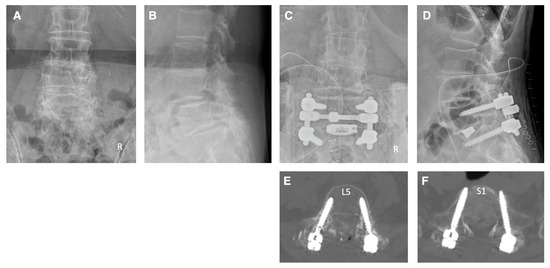

4. Illustrative Cases